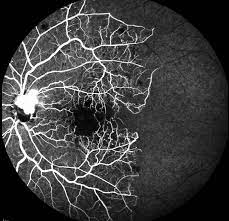

• Traitement au laser ARGON. Panphotocoagulation (PPR)  de la périphérie et laser maculaire du centre de la rétine.

Laser PPR et laser maculaire guidés par angiographie ou OCTA. Les procédures sont réalisées en consultation avec anesthésie locale par gouttes.